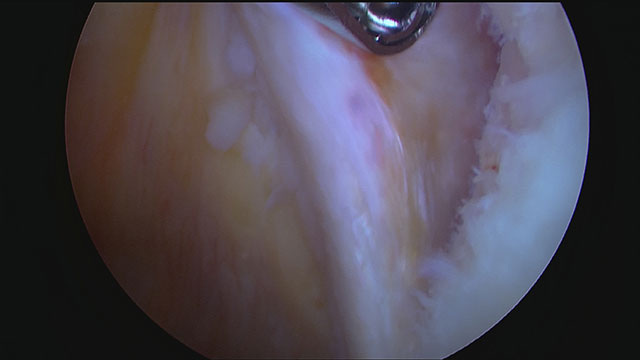

Endergebnis der Schulterstabilisierung. Das Labrum und Teile der Kapsel sind wieder fest am vorderen Pfannenrand fixiert. Gut zu erkennen ist der Wulst des Labrums und die Kapselraffung, die das Volumen im vorderen Gelenkraum verkleinert.